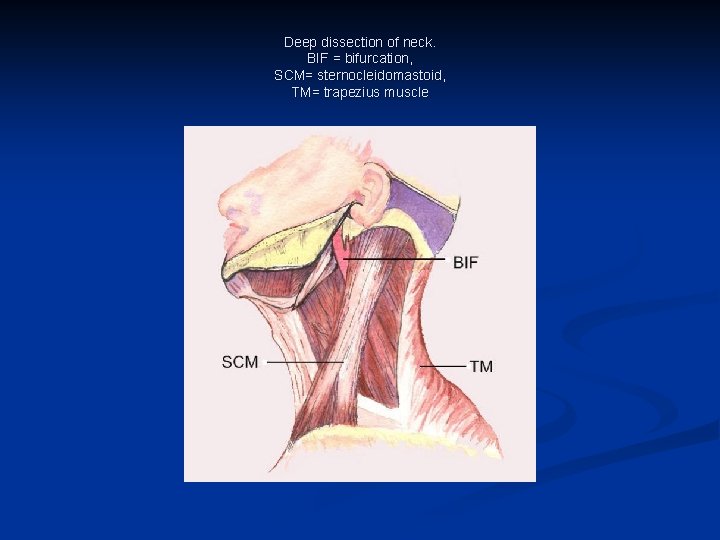

Muscles and Fascia of the Neck

Deep dissection of neck. BIF = bifurcation, SCM= sternocleidomastoid, TM= trapezius muscle